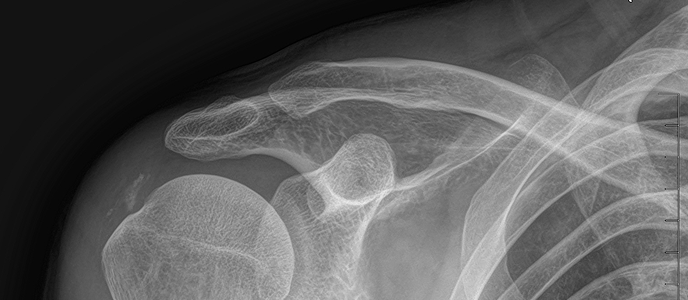

석회쇄석술 전후사진

치료 증상 갑자기 팔 들기 힘듦, 밤에 아픔

나이/성별 55세 / 남성

치료 내용 석회쇄석흡인술 후 호전

치료 기간 2024-11-22 ~ 2025-02-22